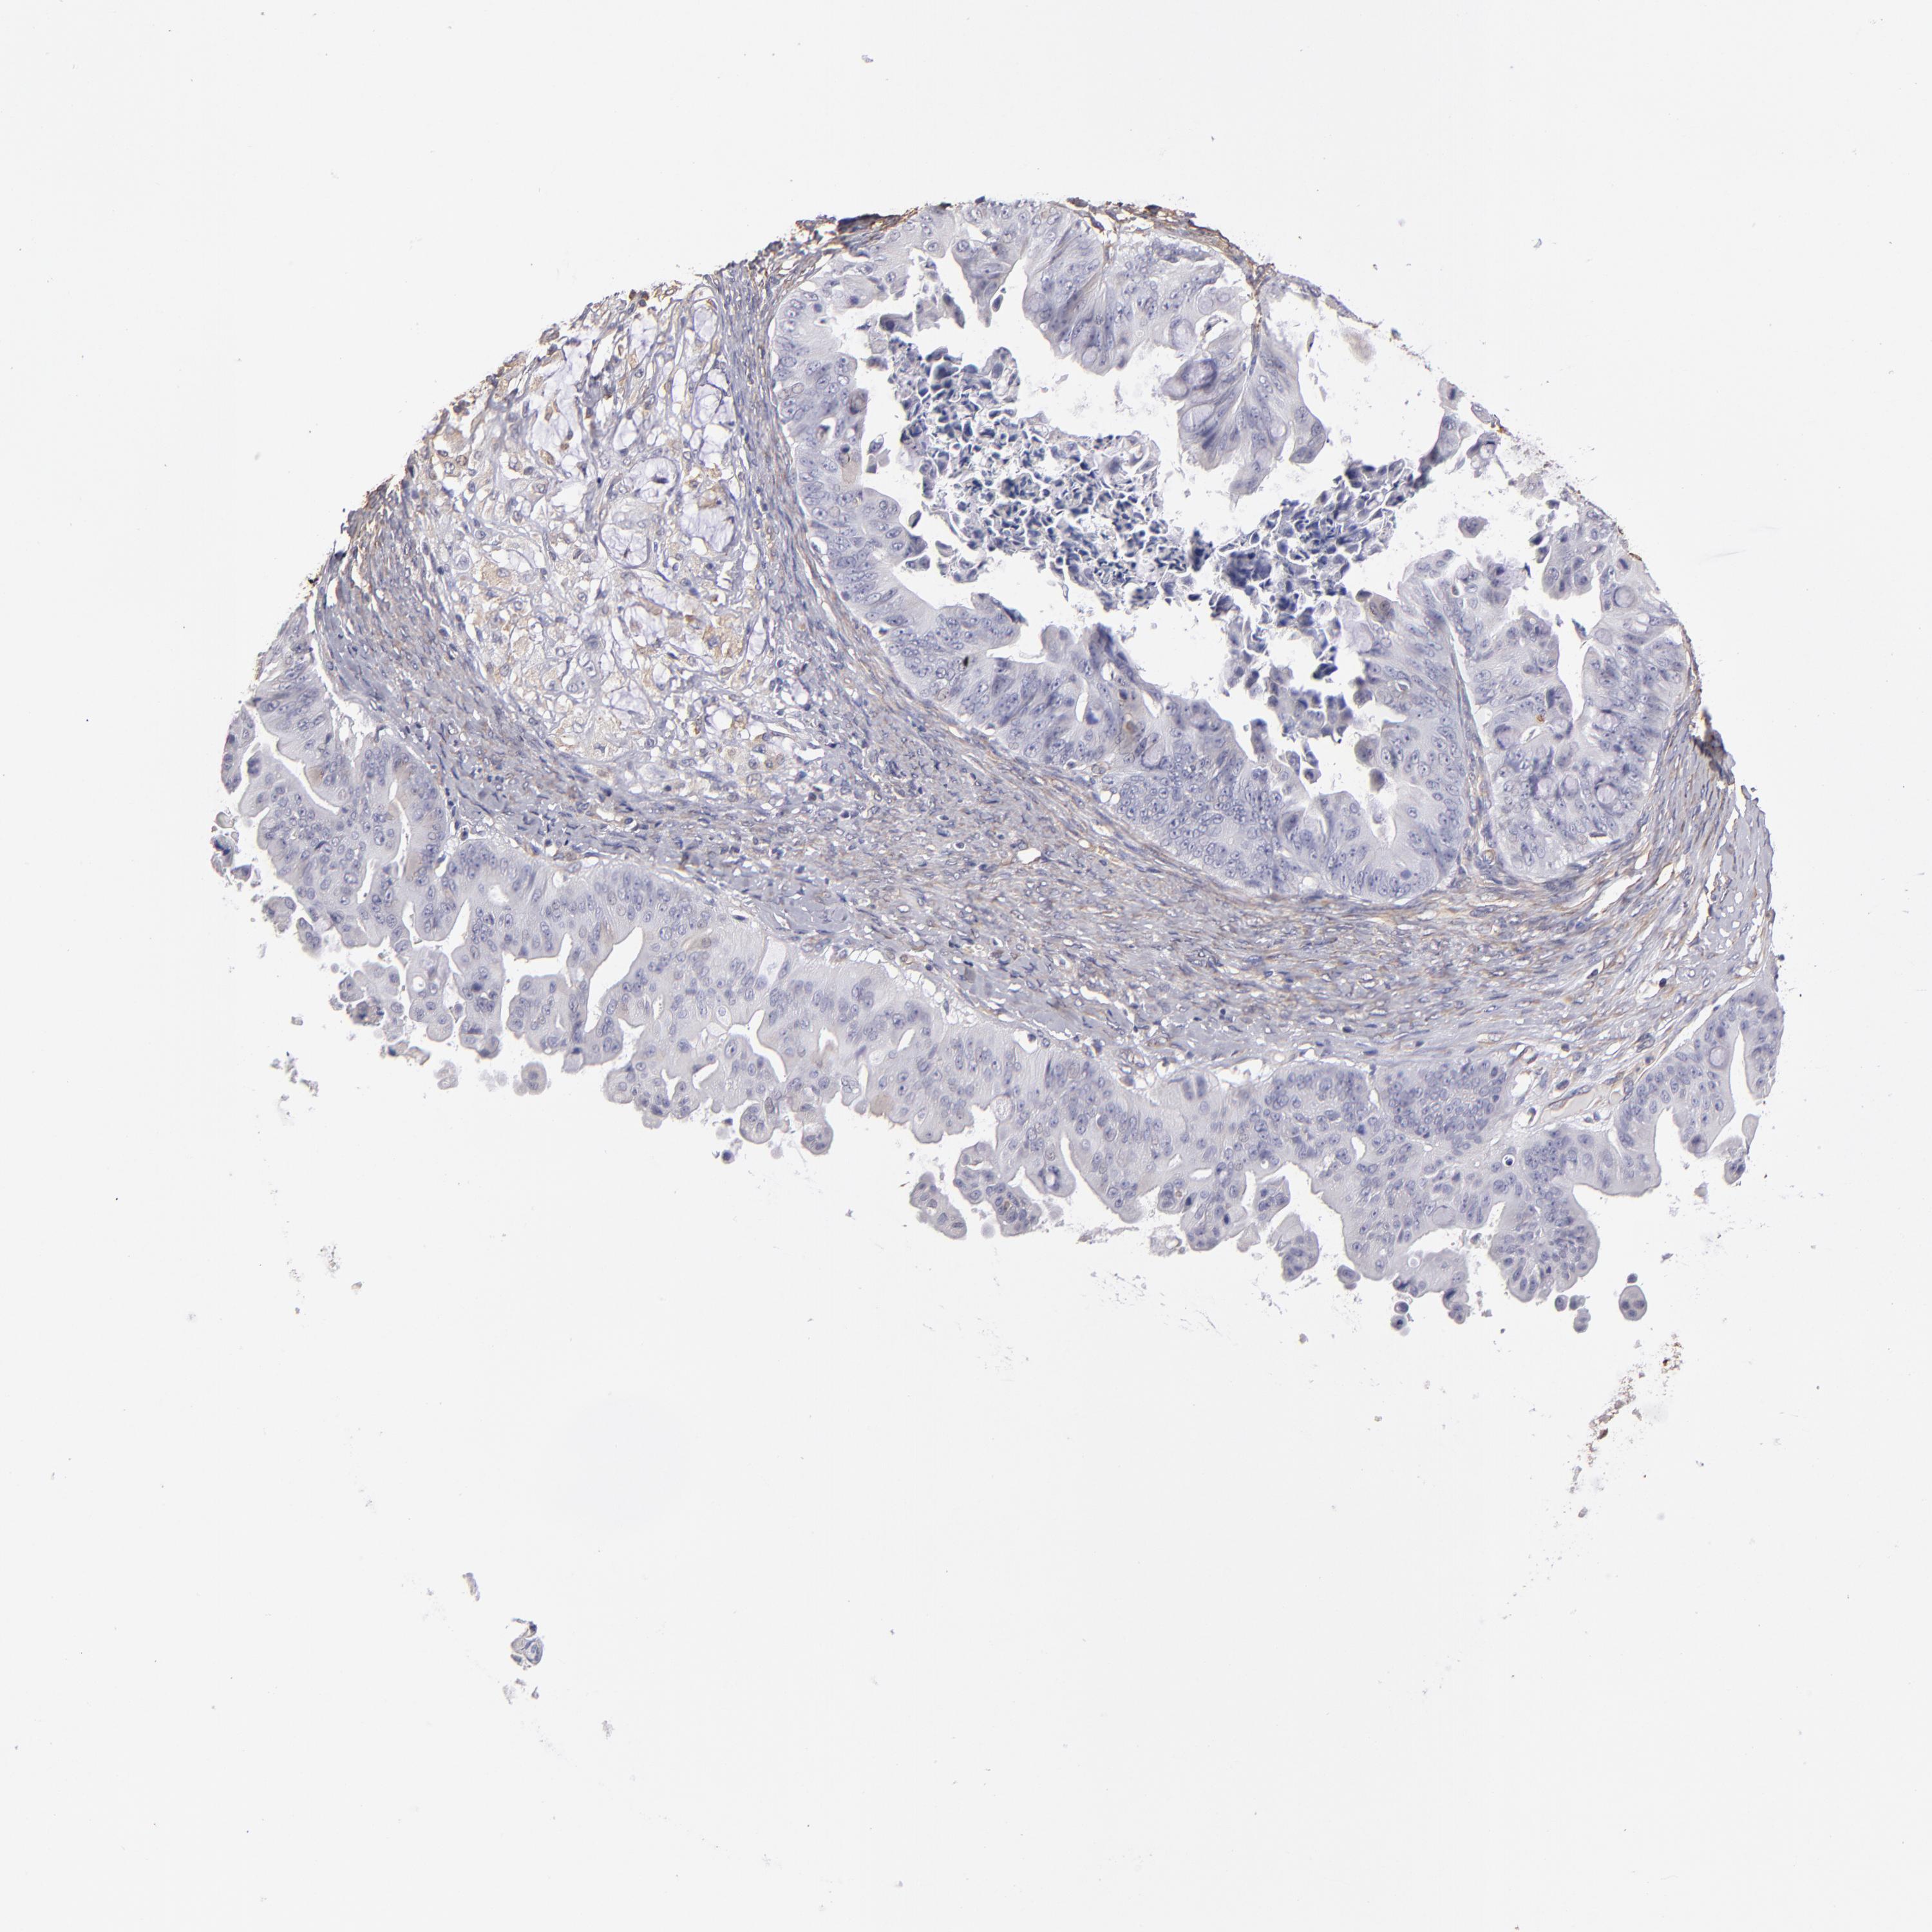

OVARIAN CANCER - Protein expressioni

A mouse-over function shows sample information and annotation data. Click on an image to view it in a full screen mode. Samples can be filtered based on level of antibody staining by selecting one or several of the following categories: high, medium, low and not detected. The assay and annotation is described here.

Note that samples used for immunohistochemistry by the Human Protein Atlas do not correspond to samples in the TCGA dataset.

Antibody stainingi

Antibody staining in the annotated cell types in the current human tissue is reported as not detected, low, medium, or high, based on conventional immunohistochemistry profiling in selected tissues. This score is based on the combination of the staining intensity and fraction of stained cells.

Each image is clickable and will lead to virtual microscopy that enables deeper exploration of all samples and also displays staining intensity scores, fraction scores and subcellular localization as well as patient and tissue information for each sample.

Antibody HPA002380

Staining

High

Medium

Low

Not detected

Intensity

Strong

Moderate

Weak

Negative

Quantity

>75%

75%-25%

<25%

None

Location

Nuclear

Cytoplasmic/membranous

Cytoplasmic/membranous,nuclear

Cystadenocarcinoma, serous, NOS

Cystadenocarcinoma, mucinous, NOS

Carcinoma, endometroid